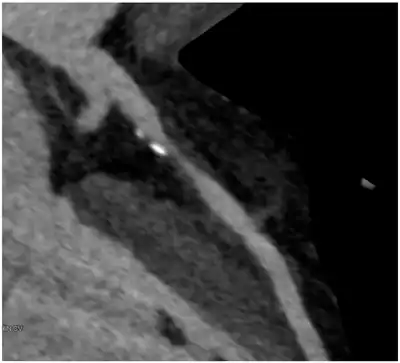

Image of contrast enhanced dual-source coronary CT-angiograph | |